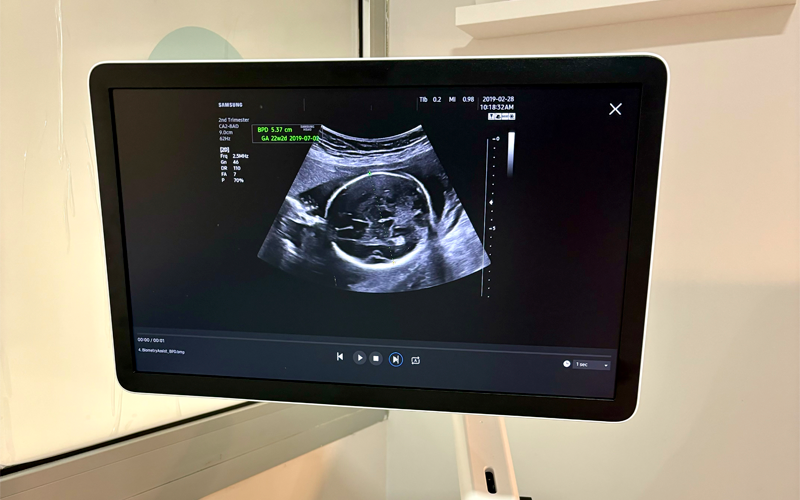

Las ecografías de seguimiento son pruebas clave que se realizan a lo largo de todo el embarazo para monitorizar el desarrollo y bienestar del bebé. Estas ecografías nos permiten obtener imágenes detalladas del bebé en diferentes fases, verificando que su crecimiento sea adecuado y que todo marche bien.

Las ecografías no solo permiten conocer mejor al bebé antes de su nacimiento, sino que también nos ayudan a detectar cualquier anomalía o complicación a tiempo. Son una herramienta imprescindible para asegurar que tanto tú como tu bebé estén saludables a lo largo del embarazo.

En nuestra consulta contamos con un ecógrafo de última generación que además nos permitirá realizar ecografías 5D del futuro bebé.